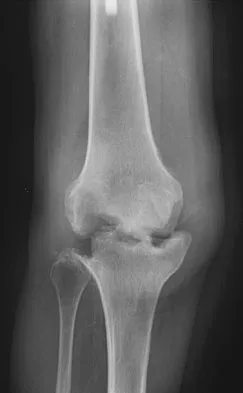

Figure 1 shows the radiograph of an 18-year-old patient who has severe knee pain. Treatment consisting of osteotomy should be perfomed